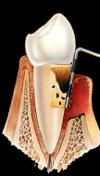

Petit à petit, et parfois sans signe visible ni douleur, l’os soutenant les dents est détruit sous l’effet des parasites, des bactéries et des globules blancs créant ainsi une poche dans laquelle du tartre s’accumule, entretenant l’inflammation et empêchant la gencive de se recoller à la racine.

L’os diminuant progressivement, le déchaussement s’accentue, les dents deviennent de plus en plus mobiles allant jusqu’à tomber.